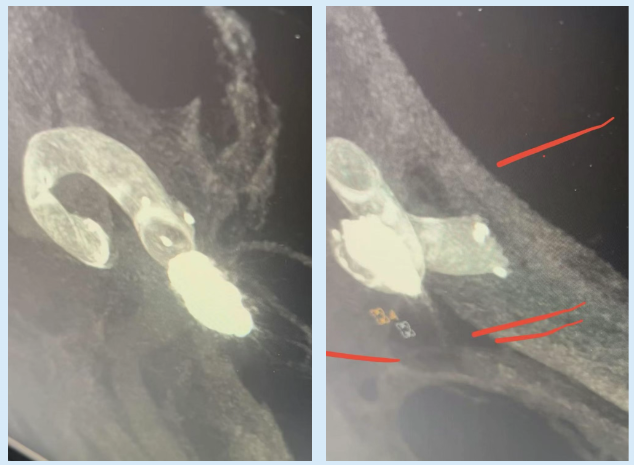

本次接受手术的是一位既往有颅内破裂动脉瘤介入治疗病史且还存在多个未破裂颅内动脉瘤的患者。此次检查发现其颈内动脉海绵窦段及眼动脉段上存在多个形态复杂的动脉瘤。这类“颅内不定时炸弹”,一旦破裂致死致残率极高。而患者高龄且身体状况不佳,无法耐受传统开颅手术的创伤与风险。

面对这一棘手难题,我院神经外科团队在董雷副院长、王德臣主任的带领下,经过反复研判,决定采用目前国内先进的“血流导向装置”(即密网支架)介入治疗方案。该技术通过大腿根部微小穿刺点,将网孔致密的特殊支架精准放置于动脉瘤开口处,如同“血管内保护伞”,改变进入动脉瘤的血流动力学,促使血液在瘤内淤滞、凝固,最终使动脉瘤自行萎缩、闭合,具有创伤极小、恢复快、安全性高的显著优势。

手术当日,我院神经外科、介入科、麻醉科1团队紧密协作,赵洪亮主任医师带领崔启韬、黄广懿、余冠东医生精准操作,顺利完成支架释放。术中造影显示,支架定位精准,贴壁良好,载瘤动脉通畅,手术圆满成功。